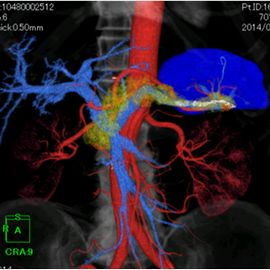

CT画像(3D)